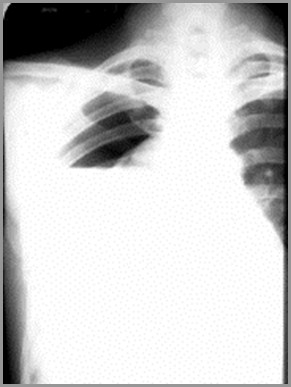

Opacified Hemithorax

If an effusion fills the entire hemithorax, itacts like a mass

There is displacement of the heart andtrachea away from the side of opacification

In atelectasis of an entire lung, the heartand trachea are pulled toward the side ofopacification

The righthemithorax isopaque

There is a shift ofthe heart andtrachea away fromthe side ofopacification

This ischaracteristic of apleural effusion

Large Right Pleural Effusion